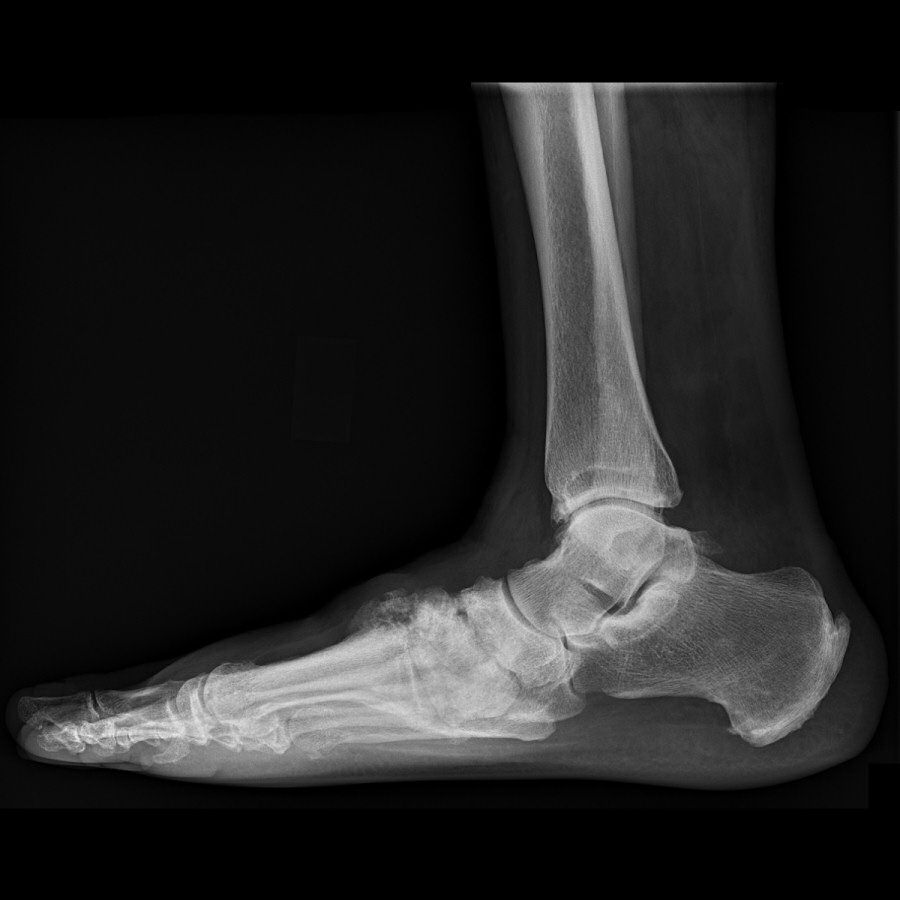

Gammal, läkt charcotfot